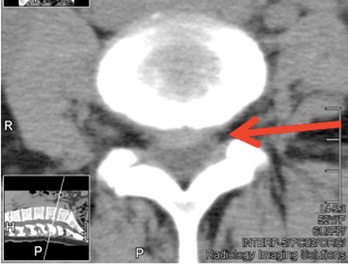

CT was ordered and shown Spinal Canal Stenosis at L4 5, and a left-sided disc prolapse with impingement of the left L4 root.

page4image1764640 page4image1761728